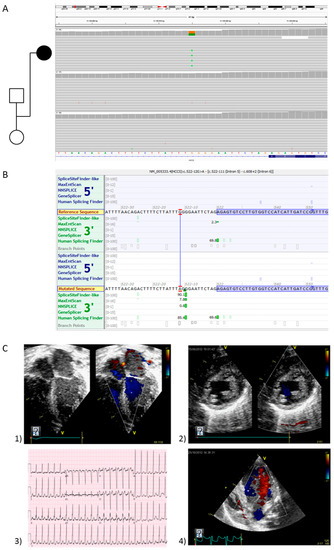

| 14 | yes | 3 | F | sHCM | Linear skin defects with multiple congenital anomalies | HCCS | ChrX:g.11139015G>A | NM_005333.4:c.522-12G>A | p.(Ala174fs*2) | hetero | de novo | Likely pathogenic |